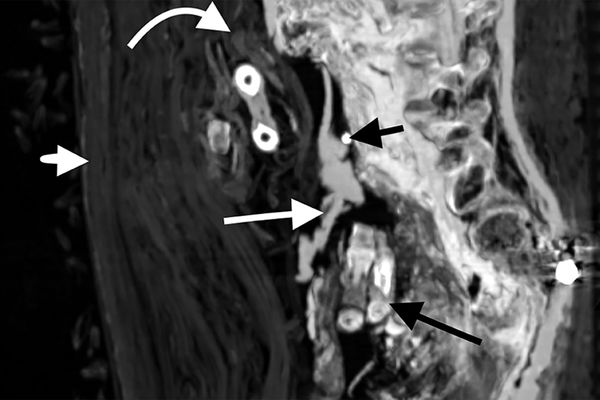

Мозг перед мумификацией не извлекался — он сохранился в черепе. Сам череп тоже был нетронут. Но внутренние органы были удалены через отверстие в боку, через него же тело было набито тканью. Сердце осталось на месте.

На иссохших глазных яблоках ученые обнаружили следы смолы. Также просмоленные кусочки ткани были в ноздрях мумии. В задней части рта сохранился язык.

При повторном захоронении мумию явно пытались «отремонтировать» — пропитанные смолой бинты фиксировали оторвавшуюся из-за перелома шейных позвонков голову, прикрывали повреждения брюшной полости. Сломанным и вывихнутым конечностям придано подходящее положение. Ступни зафиксированы с помощью деревянных дощечек.